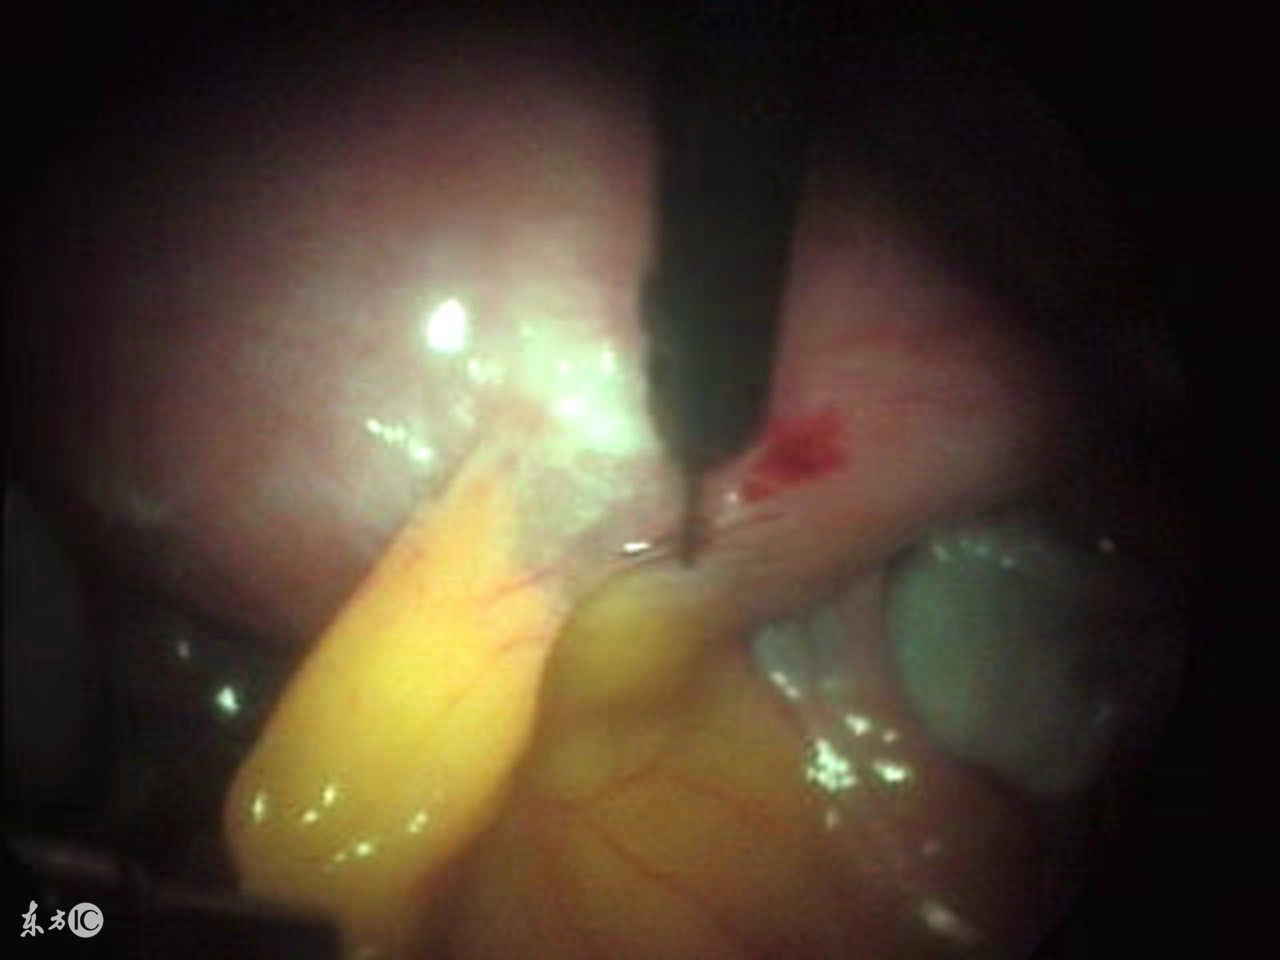

腹腔镜手术作为一种已经广泛运用在临床上的新技术,得到了广大患者的熟知和接受, 腹腔镜手术的原理是利用现代高科技医疗技术用电子、光学等先进设备原理来完成的手术,是传统剖腹手术的跨时代进步,它是在密闭的腹腔内进行的手术:摄像系统在良好的冷光源照明下,通过连接到腹腔内的腹腔镜体,将腹腔内的脏器摄于监视屏幕上,手术医师在高科技显示屏监视、引导下,于腹腔外操纵手术器械,对病变组织进行探查、电凝、止血、组织分离与切开、缝合等操作。

腹腔镜手术是一种微创手术治疗方法,创伤小,恢复快,对于许多疾病的治疗都有很好的作用,比如严重的输卵管阻塞、卵巢囊肿等可以采用腹腔镜手术来治疗,那么做腹腔镜手术需要多少钱呢?